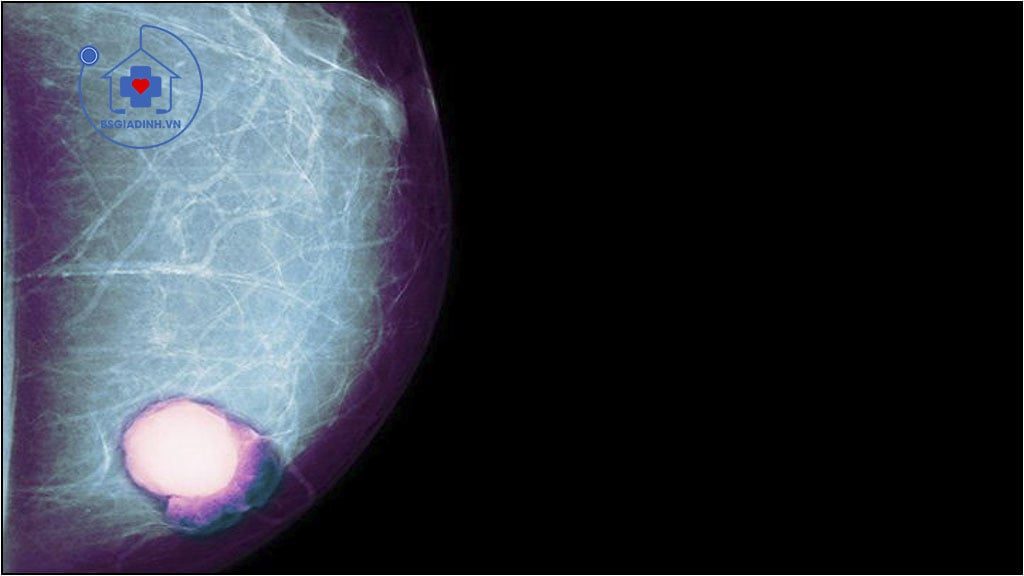

Chất chỉ điểm ung thư hay marker ung thư (tumor marker) là một chất được các tế bào của cơ thể sản xuất khi đáp ứng với sự có mặt của ung thư. Kháng nguyên ung thư 15-3 (Cancer Antigen 15-3 [CA 15-3]) là một glycoprotein được bộc lộ trên một loạt các tế bào ung thư biểu mô tuyến và tìm thầy trong máu của các Bệnh nhân bị các bệnh lý lành tính và ác tính của vú, cũng như trong các ung thư biểu mô (carcinoma) vú đã di căn tới gan và xương. Tuy vậy, nồng độ CA 15-3 cao nhất được tìm thấy ở Bệnh nhân bị ung thư vú di căn.

- Ung thư vú và ung thư vú đã di căn (khoảng 80% các ung thư vú đã di căn).

- XÉT NGHIỆM hữu ích trong chẩn đoán ung thư vú và đánh giả ung thư vú đã có di căn hay chưa. Nồng độ CA 15-3 tăng lên ở 10% các khối u lành tính của vú, 30 – 50% các ung thư vú chưa có di căn ; 70 – 80% các ung thư vú đã có di căn. Nồng độ CA 15-3 trong các tình trạng không phải là bệnh lý ung thư có xu hướng ổn định theo thời gian, trái lại trong ung thư vú di căn. nồng độ này tăng lên liên tục.